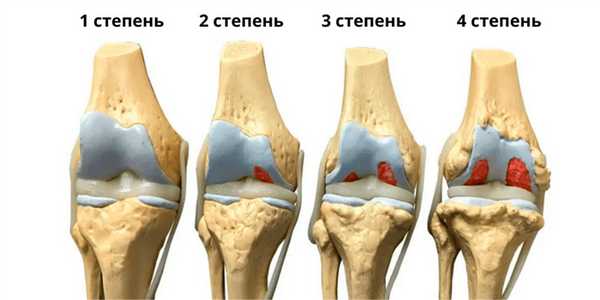

Степени коксартроза тазобедренного сустава

1 степень артроза тазобедренного сустава

Может протекать бессимптомно, иногда появляются умеренные боли после физических нагрузок, быстро исчезающие в покое. Рентгенография: изменения отсутствуют или имеется небольшое сужение суставной щели. МРТ на 1 стадии коксартроза: в хрящевой ткани появляются признаки неоднородности.

2 степень артроза тазобедренного сустава

Боли усиливаются, иррадиируют в колено, голень и голеностоп, в покое проходят не сразу. Рентген: явное сужение суставной щели и единичные разрастание костной ткани (остеофиты) по краю суставной впадины. МРТ на 2 стадии коксартроза: явные дефекты (эрозии, трещины) хряща с утратой менее половины объема хрящевой суставной ткани.

3 степень артроза тазобедренного сустава

Ногу трудно отводить в сторону и поворачивать внутрь, боли усиливаются, часто появляются в покое во сне. Болезненность в ноге при ходьбе заставляет принимать вынужденное положение тела и опираться на трость. Рентген: суставная щель еще более суживается, множество остеофитов приводит к деформации ТБС. МРТ на 3 стадии коксартроза: разрушено более половины объема хрящевой ткани. Третью стадию еще можно лечить консервативно.

4 степень артроза тазобедренного сустава

Значительная утрата суставной функции. Болит вся нога: область ТБС, пах, ягодичная область, бедро, колено, голеностоп. Развивается плоскостопие, нога укорачивается, мышцы атрофируются. Рентген: множественные крупные остеофиты, суставная щель сужена до минимума или отсутствует. МРТ на 4 стадии коксартроза: хряща нет, появляются изменения в костной подхрящевой ткани в виде уплотнения (склероза).

Степени коксартроза